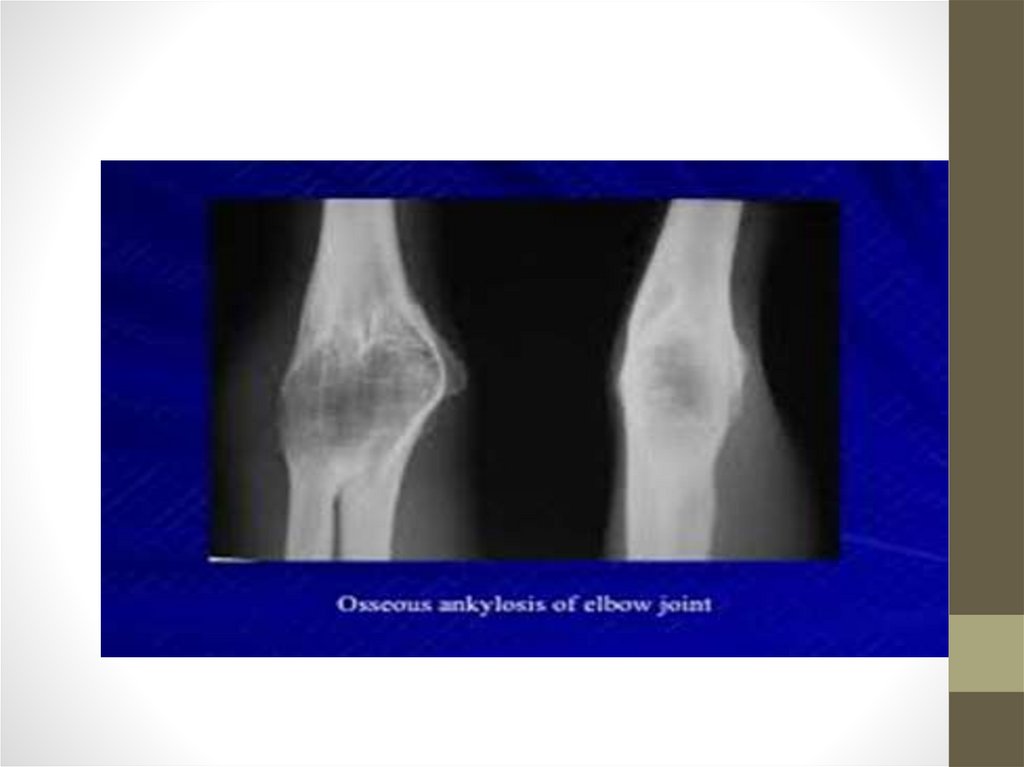

Классификация

• Костный. Становится итогом гнойных артритов и

внутрисуставных переломов. Кости в зоне сустава срастаются,

образуя единый массив. Суставная щель на снимках не

определяется, движения полностью отсутствуют.